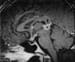

YST cells may form many histologic patterns resembling embryonal structures. The most common pattern seen in the majority cases of these tumors is microcystic structure, which is characterized by the presence of a spider-weblike network formed by vacuolated cytoplasm of tumor cells, similar to a honeycomb (see the image below). [1]

Yolk Sac Tumor Pathology. Microcystic pattern of yolk sac tumors. The tumor cells form a network connected by cytoplasm.